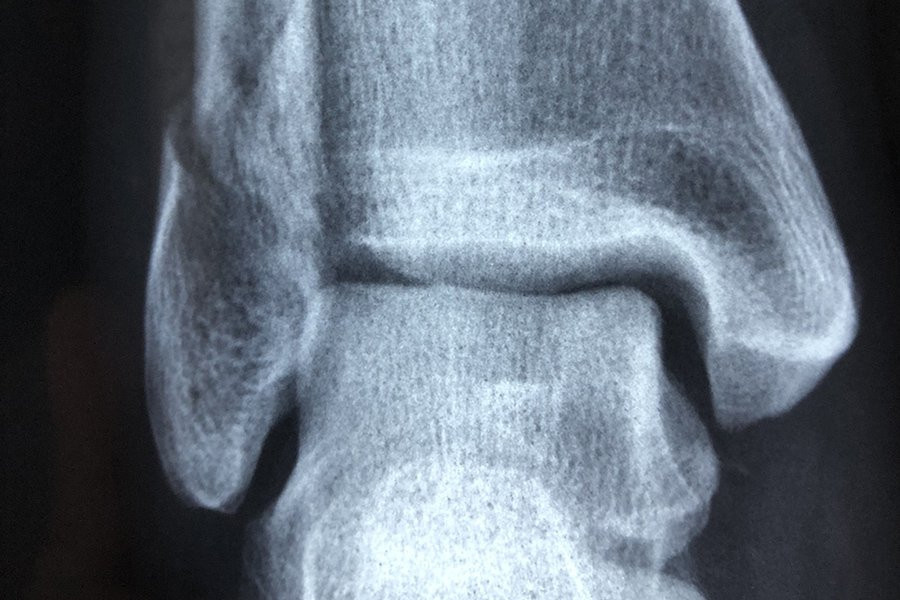

Форма коленной чашечки человека может быть индикатором того, подвержен ли он большему риску развития остеоартрита, согласно новому исследованию Австралийского национального университета (ANU). Исследование было опубликовано в журнале Osteoarthritis and Cartilage.

Используя передовые методы анализа изображений для создания 3D-моделей сотен костей коленной чашечки, команда затем применила методы моделирования формы для визуализации и измерения формы поверхностей коленной чашечки в трех измерениях.

Хотя они не нашли уникальных особенностей среди коленных чашечек женщин по сравнению с мужчинами, они обнаружили изменения в поверхностях коленной чашечки, которые были более выражены у людей с остеоартритом.

«Удивительно то, что различные суставные поверхности коленной чашечки по-разному меняют форму при остеоартрите и по мере увеличения тяжести заболевания», — сказала Уилсон.